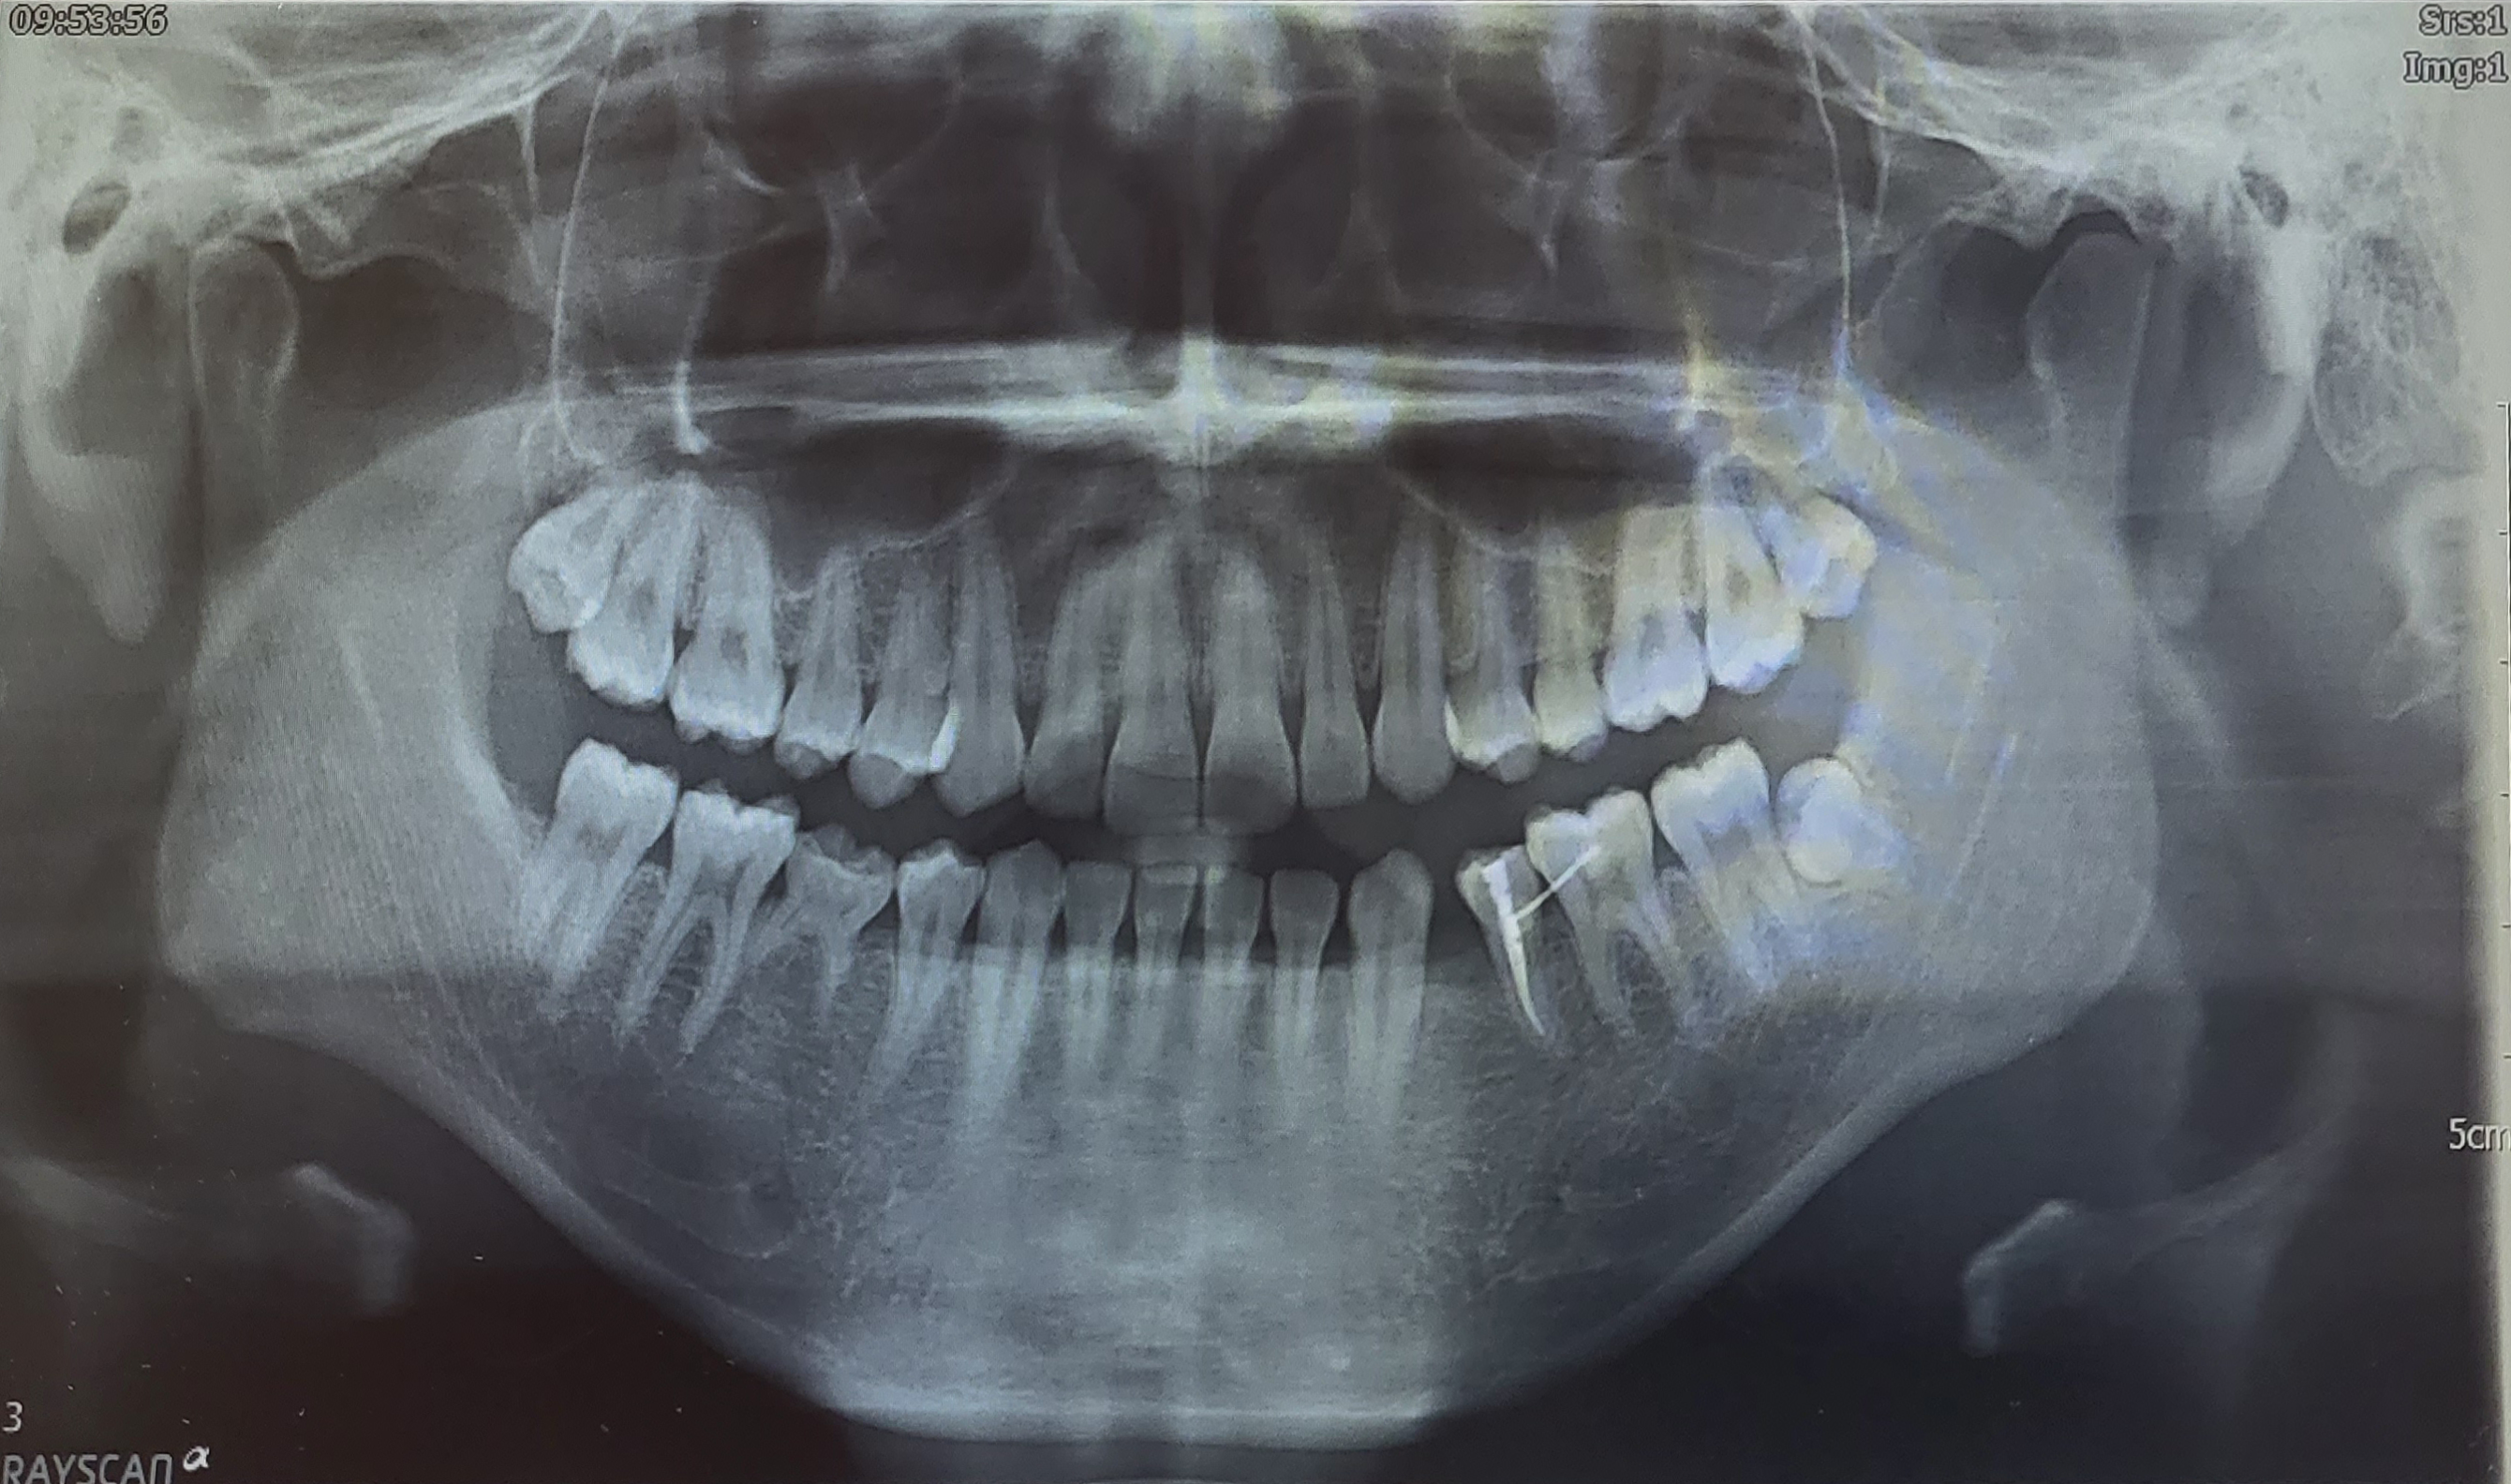

예진을 마치고 전반적인 치아를 점검하기 위해 엑스레이 촬영을 하러 같은 4층인 영상치의학과에 갔다. 접수할 때는 진료안내문을 데스크에 올려놓고 의자에 앉아 대기하면 순서가 될 때 이름을 불러주신다.

엑스레이 촬영 뒤 보존과로 가 진료를 받았다. 결과적으로 임플란트 대신 사랑니 이식으로 유치가 빠진 자리를 메우려던 내 야심 찬 결과는 개같이 멸망했다.

보존과 선생님이 말씀하신 본인의 자가치아이식이 불가능했던 이유는 다음과 같다. 우선 내 사랑니 크기와 결손 부위의 크기가 맞질 않았다. 사랑니 크기가 결손 부위의 공간에 비해 컸던 것이다. 그리고 너무 오래 전인 중학교 1학년 때 유치가 빠진 지라 결손 부위의 잇몸 뼈가 많이 얇아졌다.

4층 치과보존과 데스크에 가 접수했고 먼저 레지던트 분과 진료를 하게 되었다. 엑스레이 사진을 보고 레지던트 선생님은 이가 빠진 자리를 어금니, 사랑니까지 끌어와 교정할 수 있을 것 같다고 의견을 주셨다.

교수님이 엑스레이와 내 치아를 보고 진단한 결과 어금니, 사랑니를 끌어오는 교정이 가능하다고 말씀하셨다. 본인은 하악 좌측의 제1소구치가 결손돼 빠져버렸고 하악 우측의 제2소구치도 영구치는 없지만 유치로 버티고 있는 상태다.

내가 발치 교정을 하기에는 윗니의 치열이 매우 가지런하고 하악 우측의 제2소구치는 비록 유치지만 튼튼하게 자리잡고 있어서 뽑아내기에는 아깝다는 것이었다.

원래 윗니와 아랫니는 지그재그 형태로 맞물려 있는데 내 경우에는 어금니를 이동시키다보면 이 지그재그 형태가 맞지 않을 가능성이 높다고 하셨다. 거기다 결손된 영구치 옆의 이(하악 좌측 제2소구치)는 신경치료를 한 상태인데 신경치료를 한 경우 교정이 불가능한 경우도 있다고 한다. 다행히 나는 가능할 것이라고 했다. 이런 이유들 탓에 교과서적으로 이상적인 치료 방법은 아니지만 영구치 결손을 치료하기 위해 시행할 것이라고 말씀해주셨다.

부가적으로 현재 버티고 있는 오른쪽 아래턱의 유치에 대해서도 말씀해주셨다. 만약 하악 어금니가 빠져버린다면 교정은 못하니 그때는 임플란트를 하라고 하셨다. 파노라마 엑스레이 상으로 보이는 우측의 어금니는 크기가 크기 때문에 교정으로 당기기에는 무리가 있다고 한다.